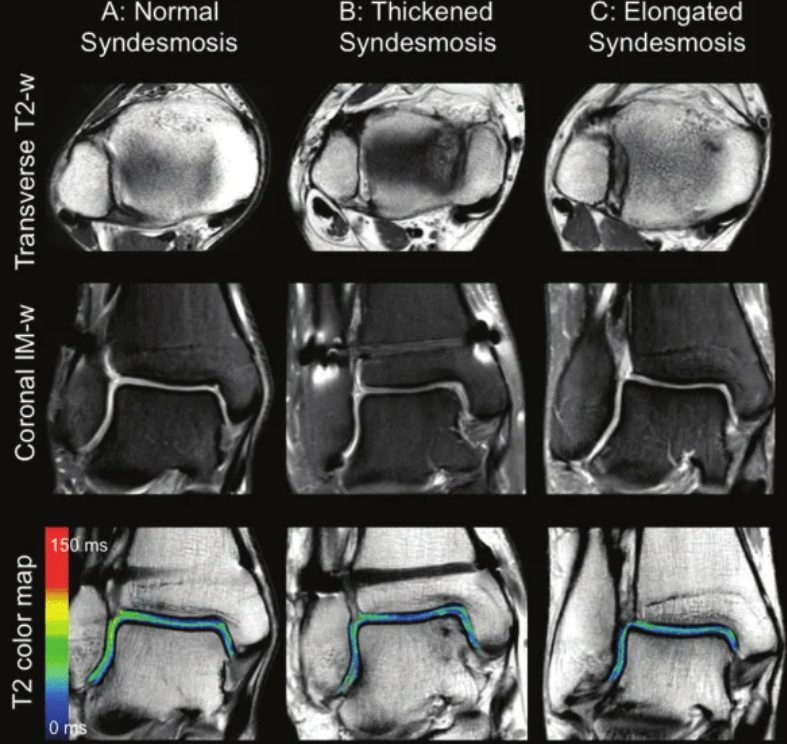

Магнитно-резонансная томография

Рис. 16. МРТ-изображение различных состояний синдесмоза: А — нормальное, В — рубцово изменённое, С — элонгированное (удлинённое)

МРТ обеспечивает более высокую диагностическую точность по сравнению с рентгенографией и КТ. В отличие от рентгенографии и КТ, которые оценивают повреждение синдесмоза по вторичным признакам, МРТ позволяет напрямую визуализировать синдесмотические связки. Контрастные препараты и МРТ 3 Тесла дополнительно повышают диагностическую точность.

Чувствительность МРТ при повреждениях синдесмоза достигает 91%, специфичность — 100%. Для сопутствующих разрывов дельтовидной связки чувствительность составляет 84%, специфичность — 93,5%.

Однако корреляция МРТ-находок с клиническими жалобами может быть затруднительной, а ценность МРТ при субклинической (subtle) нестабильности синдесмоза требует дальнейшего изучения.

В целом, рентгенография не может надёжно предсказать повреждение синдесмоза. КТ превосходит рентгенографию в выявлении подвывиха. МРТ обеспечивает чувствительность и специфичность, приближающиеся к 100%. Каждый метод имеет своё место: рентгенография — для первичного скрининга, КТ — для оценки репозиции и выявления скрытых повреждений, МРТ — для прямой визуализации связок и планирования лечения.